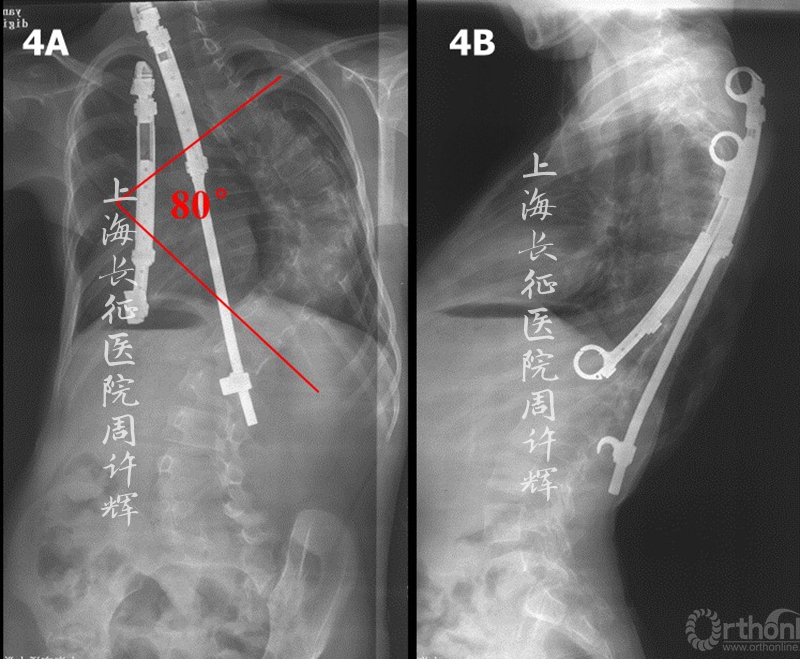

女性,3岁时发现背部畸形(图1),X片示侧弯60°。外院行支具治疗5年(8岁)后,复查全脊柱X片示支具内侧弯65°(图2)。继续外院行VEPTR(第4-9肋、第2肋-第2腰椎)治疗,术后侧弯69°(图3)。术后2年(10岁)复查发现侧弯80°、VEPTR第9肋骨折、第2肋脱钩(图4)。进行内固定更换,VEPTR(第4-10肋、第4肋-第2腰椎),术后3年(13岁)复查示侧弯90°(图5)。